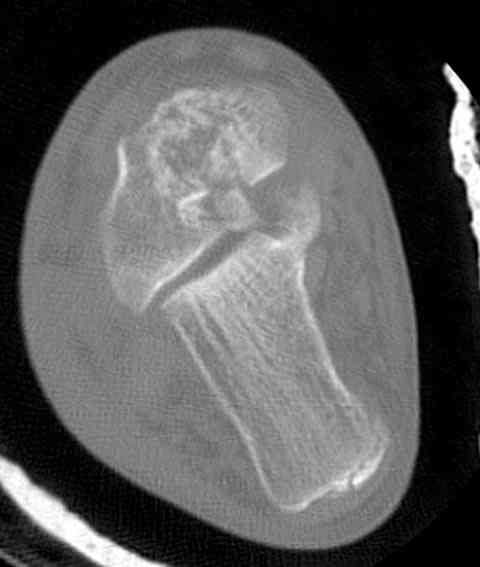

Случай с множественным оскольчатым переломом тарана оперированный из двойного доступа.

Через 2 мес.: